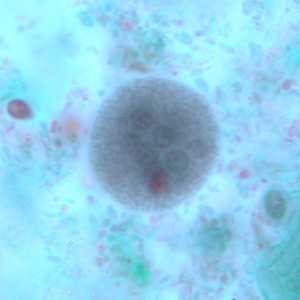

E. coli cysts stained with trichrome.

Figure A: Immature cyst of E. coli, stained with trichrome. Notice the presence of only two nuclei, and a large glycogen vacuole.

Figure B: Mature cyst of E. coli, stained with trichrome. Five nuclei are visible in this focal plane.

Figure C: Mature cyst of E. coli, stained with trichrome. In this specimen, at least five nuclei are visible in the shown focal plane.

Figure D: Mature cyst of E. coli, stained with trichrome. In this specimen, at least five nuclei are visible in the shown focal plane.

Figure E: Mature cyst of E. coli, stained with trichrome. This figure and Figure F represent the same cyst shown in two different focal planes. Eight nuclei can be seen between the two focal planes. Also, above the cyst in this figure, a trophozoite of Endolimax nana can be seen.

Figure F: Mature cyst of E. coli, stained with trichrome. This figure and Figure E represent the same cyst shown in two different focal planes. Eight nuclei can be seen between the two focal planes.